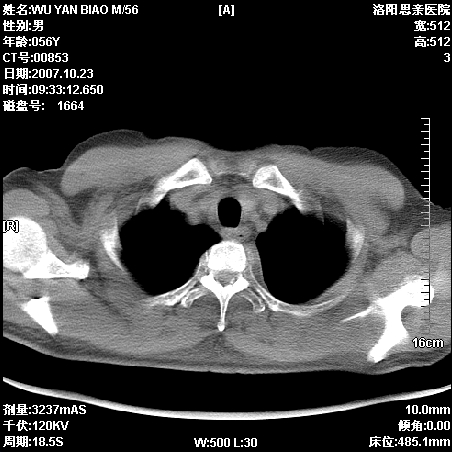

后上纵隔占位,与肺交界清,宽基底附着脊柱,密度均匀,局部骨质无明确改变.

考虑;神经源性肿瘤,---起源交感n链?,不除外肠源性囊肿.

与纵隔关系密切,密度均匀。只能考虑:后纵隔神经原性肿瘤!

后纵隔神经原性肿瘤可能性大,孤立性胸膜间皮瘤待排.

1、病灶在后纵隔脊柱旁沟内,此处是神经原性肿瘤的好发部位

2、病灶边缘光滑整齐,更说明病灶来于纵隔,由于有胸膜的包裹所以才导致这么光滑的边缘

3、病灶内的密度均匀